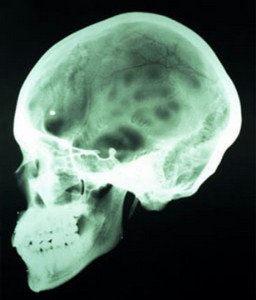

Перелом основания черепа — повреждение черепа, являющееся переломом одной или нескольких костей, входящих в основание мозгового отдела черепа — затылочной, височной, клиновидной и решетчатой.

Переломы основания черепа подразделяются на переломы передней и задней части основания. Первый тип включает повреждения клиновидной и решетчатой костей. Второй — повреждения затылочной, височной, и задней части клиновидной костей. Перелом височной кости встречается в 75% переломов основания черепа и может быть продольным, поперечным или смешанным, в зависимости от положения линии перелома относительно продольной оси пирамидки височной кости.[4]

Повреждения затылочной кости вблизи большого затылочного отверстия (‘foramen magnum’) сопряжены с риском повреждения спинного мозга, нервов и крупных кровеносных сосудов вблизи отверстия.[5]